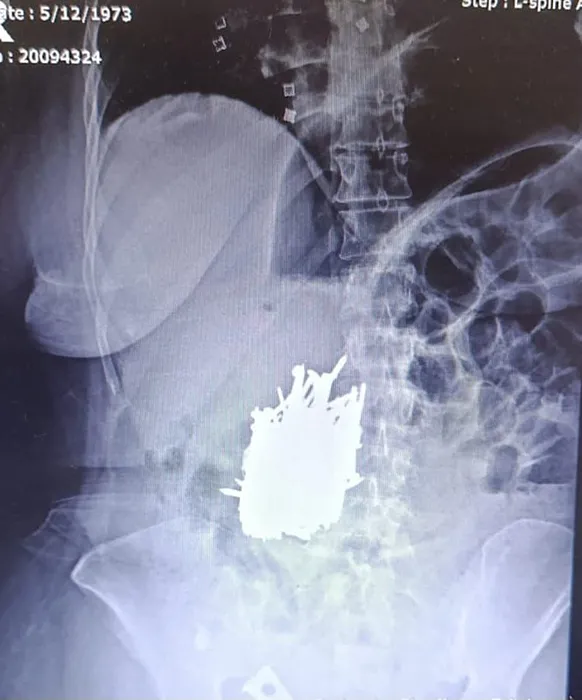

Zihinsel engelli A.K., karın ağrısı şikayetiyle Erdemli Devlet Hastanesi’ne gitti. Hastaya yapılan tetkik sonucunda kadının midesinde çok sayıda metal cisim olduğu tespit edildi.

Hasta, genel cerrahi uzmanı Dr. Can Terzier ve ekibi tarafından acilen ameliyata alındı ve midesinden yaklaşık 1 kilo ağırlığında çivi, inşaat demiri, kolye, toka gibi çok sayıda metal cisim çıkarıldı.

Hastanın ameliyatının başarılı geçtiğini, şu anda sağlık durumunun stabil seyrettiğini ve servise alınarak takibinin devam ettiğini belirten Dr. Terzier, zihinsel engeli bulunan hastaların asla yalnız bırakılmaması gerektiğini belirterek, hasta yakınlarının bu konuda duyarlı olmasını istedi.